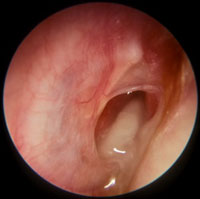

Injected Tympanic Membrane

Pink/red tympanic membrane

Often seen with fever, eustachian tube obstruction or viral URTI

Tympanic membrane is transparent (no effusion)

The handle of the malleus is visible and more horizontal